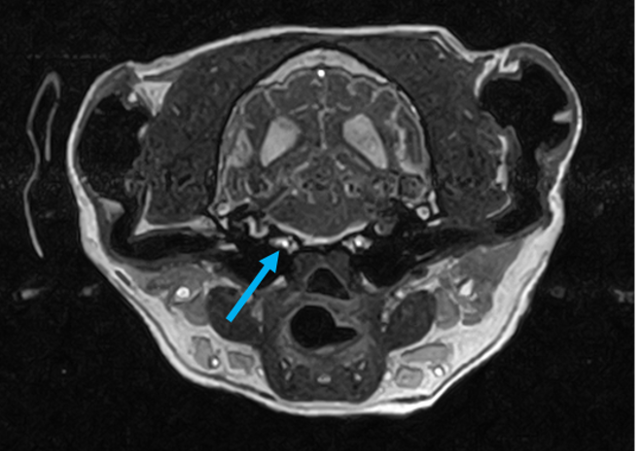

W obrębie kanału kręgowego najczęstszymi wskazaniami do badania rezonansem magnetycznym u zwierząt są:

• proces nowotworowy

• ocena rdzenia kręgowego, splotów i nerwów rdzeniowych

• ocena przepukliny i stopnia ucisku na rdzeń kręgowy

• dyskopatie, neuropatie, radikulopatie

• urazy kręgosłupa

• zwyrodnieniowe zwężenie lędźwiowe krzyżowe (DLSS)

• spondylomielopatia szyjna

• malformacje Chiariego

• wady złącza czaszkowo mózgowego